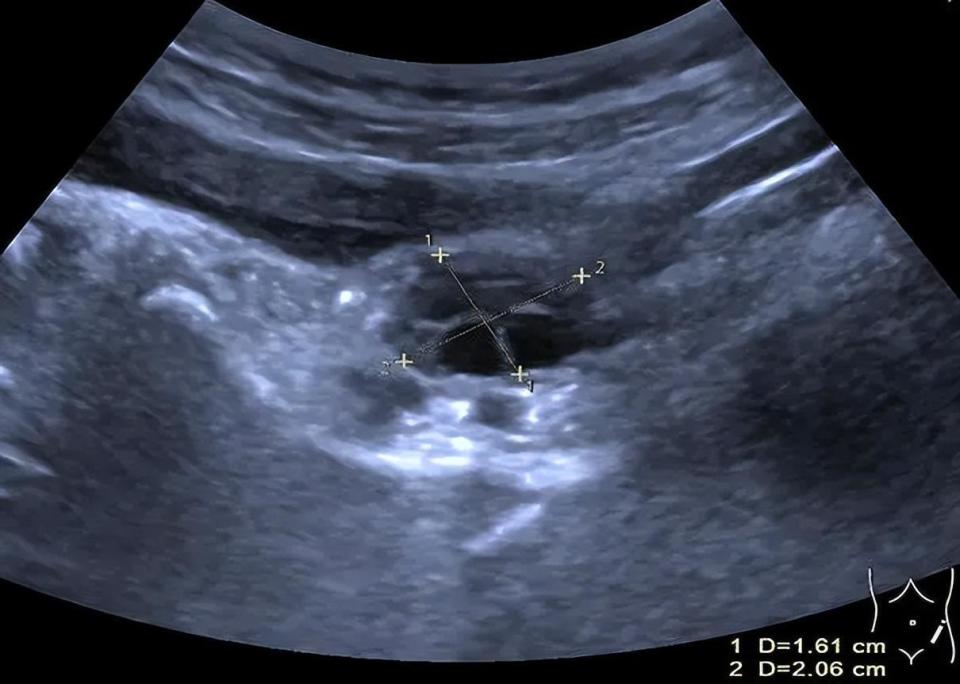

图片

▲右侧卵巢体积约3.2ml,内见4个直径大于4mm卵泡